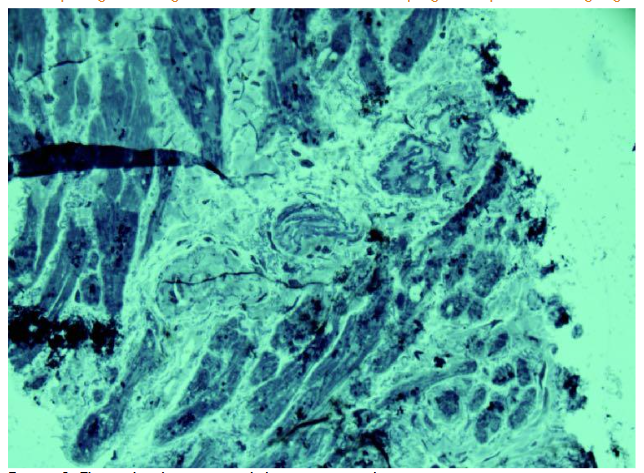

The obtained images of arterioles were characteristic for each individual patient, showing both similarities and differences. The arterioles displayed variable lumen diameters, ranging from very large to small profiles. Wall thickness also varied, with some arterioles showing pronounced intussusceptive invaginations into the lumen. In certain cases, bridges connecting opposite arteriolar walls were observed, sometimes multiple in a single vessel.

Atherosclerotic changes were particularly notable in larger arterioles. These vessels exhibited elongated lumens, significant wall thickening, and abundant smooth muscle cells. Some large arterioles showed up to two convolutions at different ends of the lumen. Evidence of newly forming arterioles was observed, including residual fragments indicating separation. Notably, the newly separated arterioles differed markedly in lumen size compared to the parent vessel. In some separated segments, chambers were present, indicating the formation of a new convoluted vessel.

The observed arteriolar growth sometimes resulted in highly irregular forms. Formation of pseudo-vessels occurred through protrusion of one arteriolar wall into the lumen, and growing walls occasionally created new vessels with dual lumens.

Beyond varying degrees of wall thickening, significant alterations were observed in arterioles consistent with intussusceptive arteriogenesis.